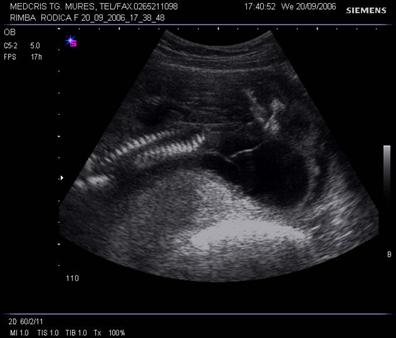

Fig . nr. 244 Higroma cystic la o sarcina cu anasarca , cu fat mort intrauterin, cu lungimea femurului corespunzatoare la 17 sapt. , sectiune longitudinala

Fig nr.246. Angularea coloanei vertebrale la fatul mort intrauterin , cu higroma cystic si hidrops